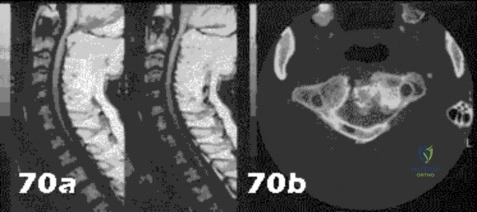

- Central cord syndrome

- Anterior cord syndrome

- Posterior cord syndrome

- Brown-Sequard syndrome

- Cervical nerve root injury